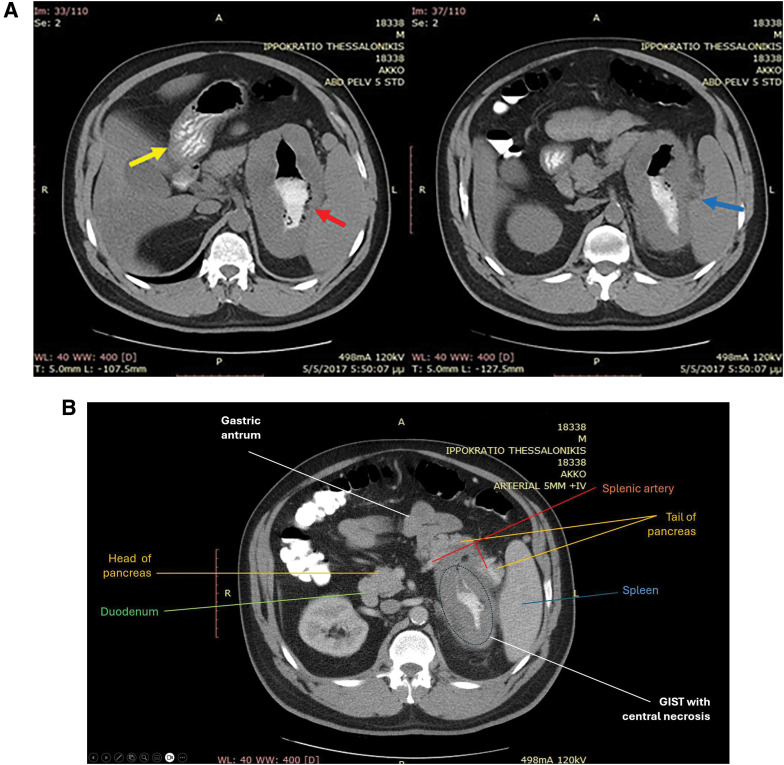

Case presentation: We describe a case of a 46-year-old male patient who presented to the emergency department with symptoms of upper gastrointestinal tract hemorrhage. Initial endoscopic findings suggested a large gastric diverticulum. Surprisingly, further investigation with computed tomography and a second endoscopy with biopsy sampling revealed that the stomach wall outpouching was actually a disguised, oversized gastric GIST. The patient underwent a posterior wall sleeve gastrectomy en bloc with the mass, the spleen, and the tail of the pancreas and recovered uneventfully. Daily administration of imatinib as adjuvant therapy was included in the treatment plan. No recurrence was observed even up to the 4-year follow-up period.